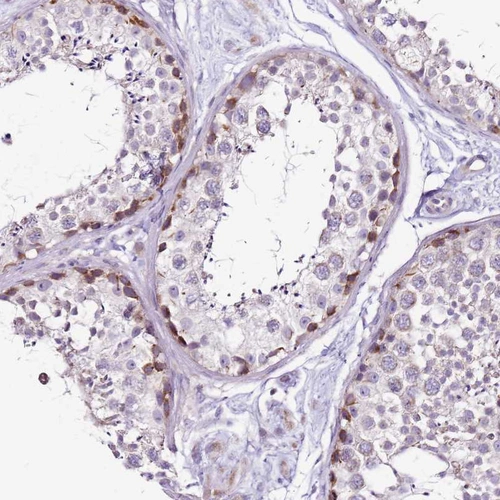

Immunohistochemical staining of human testis shows moderate granular cytoplasmic positivity in subset of cells in seminiferous ducts.